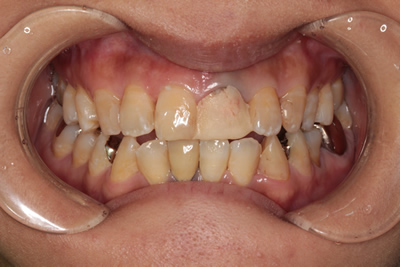

金属の土台(メタルコア)が入っていたため、硬い金属の土台が楔の役割をして、歯が割れてしまった例です。 このような深い破折の場合、通常は抜歯にいたることがほとんどです。 しかし、本症例はファイバーコアとセラミックスクラウン(被せ物)にBTAテクニックを適用し、抜歯せず保存を図り術後2年以上経ちますが大きなトラブルもなく維持されています。